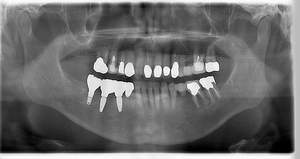

レントゲン写真

- 透過像

| 治療方針 | 右下の当該歯は歯根破折により保存不可能と診断しました。歯周疾患も伴っていたため抜歯後に骨吸収※1が大きく起こることが予測できました。チタンメッシュ併用骨再生誘導法(GBR※2)を選択しインプラント埋入と同時に行い自然な歯槽骨のラインを再現しました。またGBRを行う際にインプラント辺縁の付着歯肉の減少が起こる為、遊離歯肉移植術(FGG※3)を行い清掃性を考慮した形態に仕上げました。 ■治療方針の解説 治療した右下の歯をレントゲンで撮影したところ根本の部分に黒く写る箇所があり「根尖性慢性周囲炎※1」と診断。また歯周病も進行していました。 ※1 骨吸収・・・歯槽骨という歯を支える骨がなくなっていくこと |